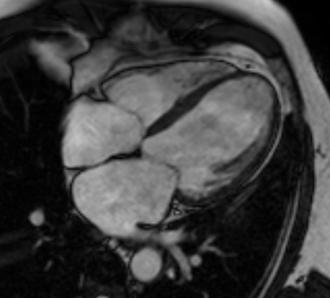

Cardiac MRI — 4-Chamber Cine (Infarct)

Four-chamber cardiac MRI cine showing myocardial infarction with wall motion abnormality

MRI Downloaded 2026-03-15

Mri

Cine 4ch

Wikimedia Commons: 4CH cine infarct.gif